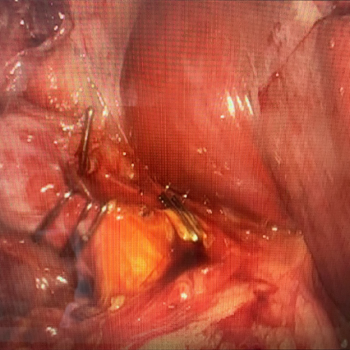

Si tienes cálculos o piedras en la vesícula biliar, debes operarte para evitar complicaciones como colecistitis o inflamación y

dolor de la vesícula, perforación de la vesícula, obstrucción de los conductos biliares por cálculos, pancreatitis y cáncer de vesícula.

“Todos los procedimientos quirúrgicos son realizados en quirófanos de hospitales certificados”.